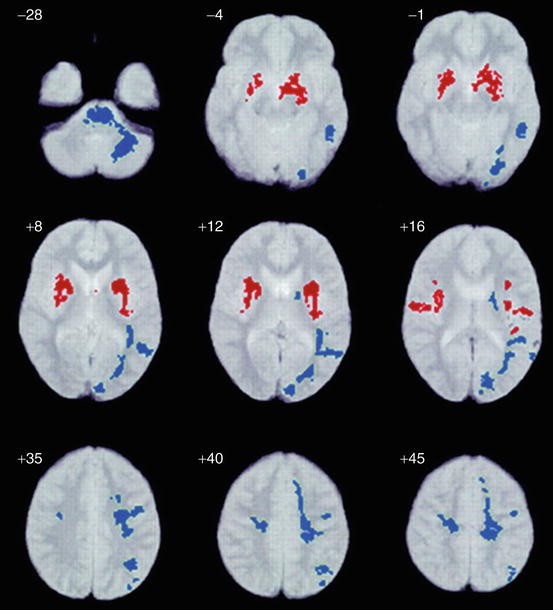

White Matter Brain Structure in Asperger's Syndrome ...

White Matter Brain Structure in Asperger's Syndrome ... from media.springernature.com